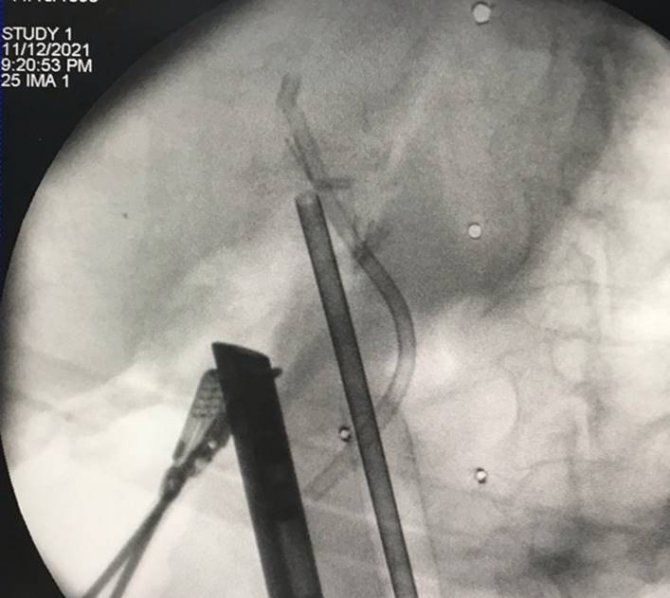

Düzce Üniversitesi Hastanesi'nde safra yolu hastalıklarının ameliyatsız tedavisinde mevcut tekniklerin iyileştirilmesi ve yeni tedavilerin geliştirilmesi ile ilgili bilimsel çalışmalar ve araştırmalar yapan Öğretim Üyeleri Doç. Dr. Serkan Torun, Dr. Öğretim Üyesi Salih Tokmak ve Dr. Öğretim Üyesi Mehmet Fuat Çetin, daha önce denenmemiş bir operasyonun riskleri ve getirileri hakkında bilgilendirdikleri hasta ve yakınlarının onayıyla işleme başladı. Ameliyathanede genel anestezi altında gerçekleştirdikleri işlemde cerrah Dr. Mehmet Fuat Çetin, laparoskopi yöntemiyle önceki ameliyatta konulmuş olan metal dikişleri çıkardı. Daha sonra gastroenteroloji uzmanları Doç. Dr. Serkan Torun ve Dr. Öğretim Üyesi Salih Tokmak'ın endoskopla safra kanalının ince bağırsağa aktığı delilikten batın içine karaciğer altına yönlendirdikleri kılavuz tel, cerrahi ekip tarafından tutularak karaciğerin içine gönderildi. Öğretim üyeleri, bu kılavuz tel ve hareketli röntgen vasıtasıyla ana safra damarında kesilerek çıkarılmış olan kısmın bütünlüğünü sağlayacak şekilde stent yerleştirdi.

Hastanın sağlık durumu hakkında bilgi veren Doç. Dr. Serkan Torun, "Operasyonu başarılı geçen hasta sorunsuz bir şekilde birkaç gün sonra taburcu edildi. Haftada en az bir kez hasta ile telefonda görüşüldü, 2 haftada bir ise laboratuvar testlerini yaptırarak bize mail attı; hiç bir sorun görünmüyordu. 2 ay sonra hastanemize kontrole geldi; şikayeti yoktu. Hasta ERCP işlemine alınarak önceki stent daha büyüğü ile değiştirildi. 2 ay sonra tekrar kontrole gelen hastamızın şikayeti yoktu, görüntüleme ve laboratuvar testleri normaldi" dedi.